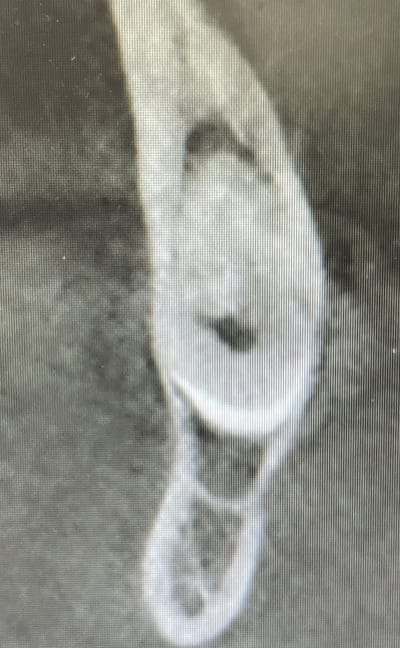

> J ai vu vendredi un Monsieur qui était révolté contre la profession car il

> devait attendre 3 semaines pour pouvoir faire retirer la 38.

Ouais... Ben celle là bon courage pour l'extraire sans emporter le nai avec....

Il a passé un cone beam?

Quels symptômes ?